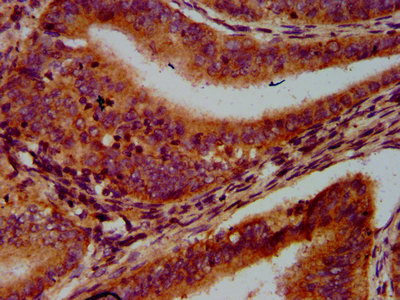

IHC image of CSB-PA757083LA01HU diluted at 1:600 and staining in paraffin-embedded human endometrial cancer performed on a Leica BondTM system. After dewaxing and hydration, antigen retrieval was mediated by high pressure in a citrate buffer (pH 6.0). Section was blocked with 10% normal goat serum 30min at RT. Then primary antibody (1% BSA) was incubated at 4°C overnight. The primary is detected by a biotinylated secondary antibody and visualized using an HRP conjugated SP system.